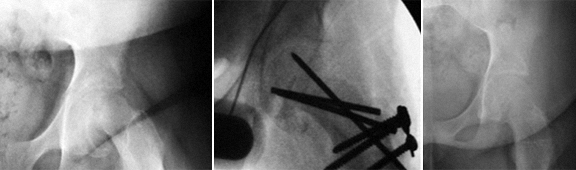

O que aconteceu na epifisiólise foi um descolamento pela zona da cartilagem de crescimento, com o subsequente deslizamento da cabeça para baixo e para trás (para posteroinferior) em relação ao colo femoral.

.jpg)

O estudo imagiológico é feito com Rx e se necessário a TAC.

O doente sintomático é candidato a cirurgia conservadora da anca e é efectuado tratamento cirúrgico que consiste em recolocar a cabeça femoral em posição o mais anatómica possível, e com a técnica cirúrgica da “luxação segura”.

B - DOENÇA DE LEEG-CALVÉ-PERTHES